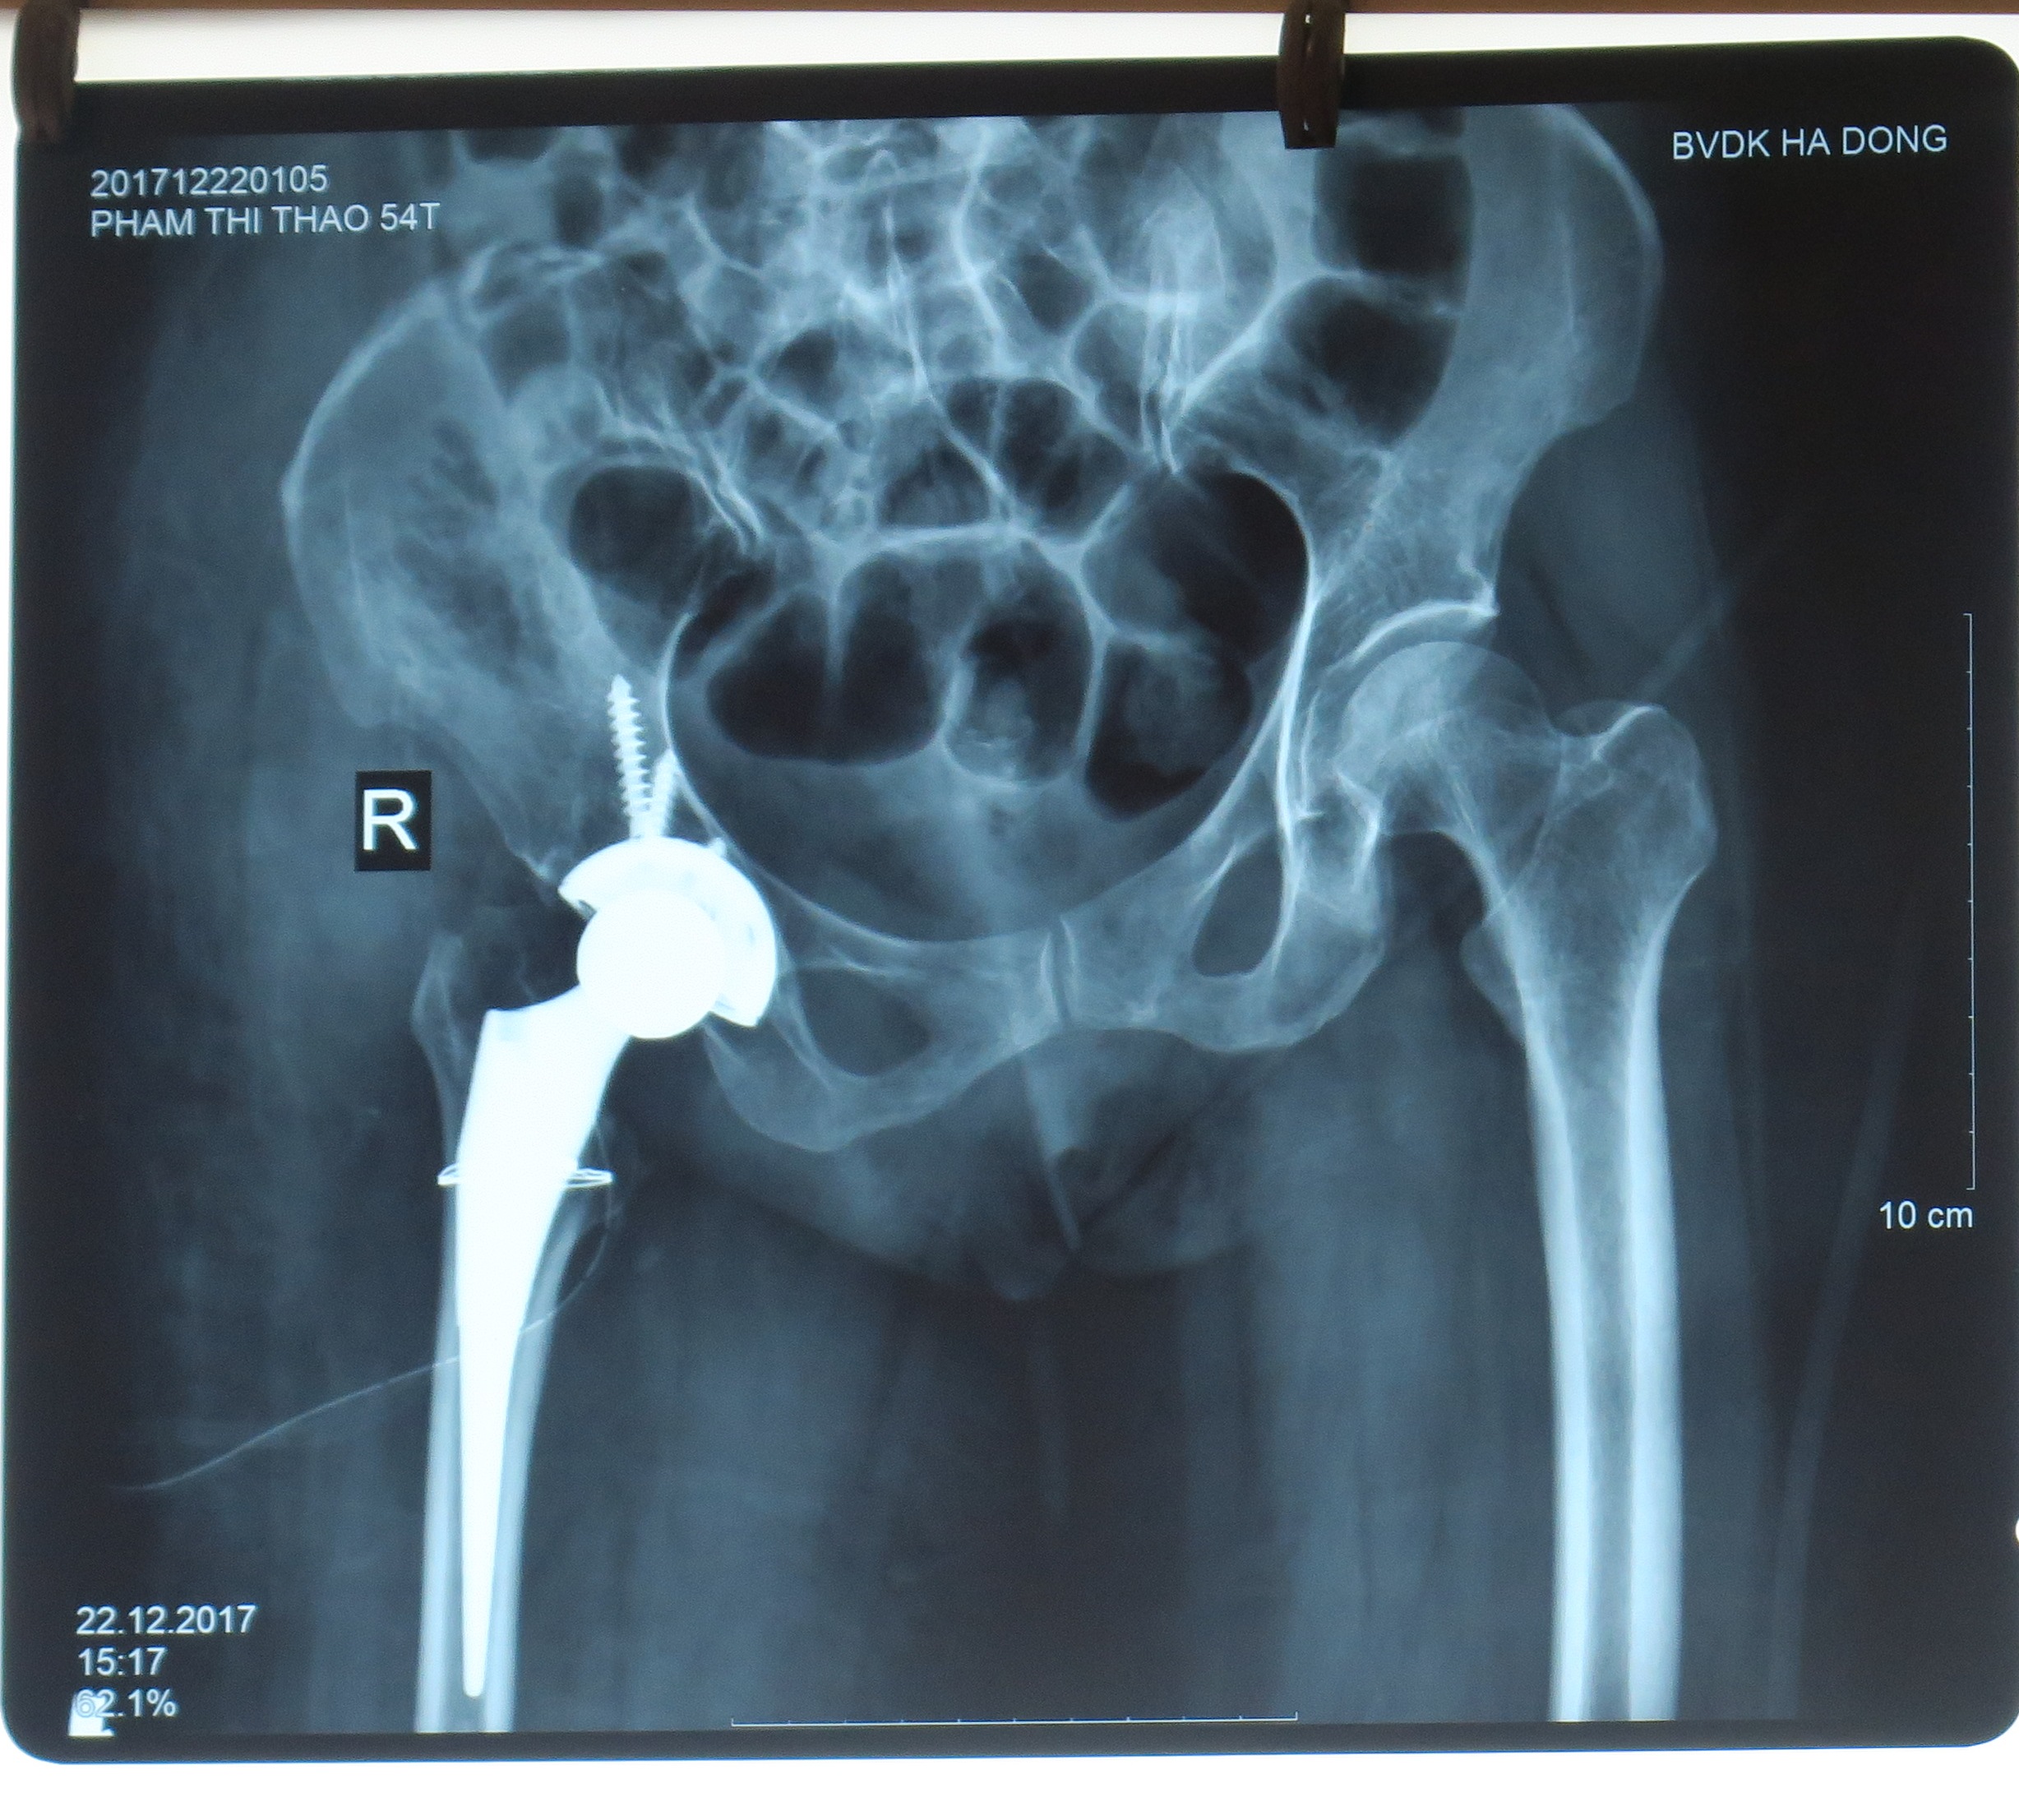

Hình ảnh khớp kháng của bệnh nhân Thao trước và sau khi thay

BSCKII Trần Quang Toản người trực tiếp phẫu thuật cho bệnh nhân Thao cho biết: trước khi mổ chúng tôi phải hội chẩn và tính toán rất cặn kẽ đưa ra nhiều phương án để cân nhắc lựa chọn. Bởi suốt 48 năm chỏm xương đùi đã thích nghi tại vị trí bị trật mới hình thành nên một ổ khớp mới tại vị trí trật này. Còn tại vị trí ổ khớp cũ đã biến dạng teo nhỏ lấp đầy tổ chức xơ. Cấu trúc xương đùi, xương chậu, cột sống biến dạng theo. Kèm theo đó các cấu trúc xung quanh: cơ, dây chằng, bao khớp cũng co ngắn xơ dính co kéo. Lựa chọn thay khớp nhân tạo đặt tại vị trí ổ khớp mới hay đặt lại vị trí giải phẫu cũ của bệnh nhân là bài toán khó cần phải đươc tính toán tỉ mỉ. Để ca mổ có kết quả tốt nhất cho bệnh nhân chúng tôi quyết định đặt 1 đinh xuyên qua đầu giới xương đùi trên hệ thống ròng rọc kéo dài trục chi để lấy lại độ dài tối đa có thể của chi làm cho cơ gân giãn ra trước mổ. Và cuối cùng chúng tôi đã đưa được khớp về vị trí giải phẫu ban đầu trước khi trật. Kết quả đôi chân đã dài gần bằng nhau chứ không phải lệch 4 và 5 phân như ban đầu.